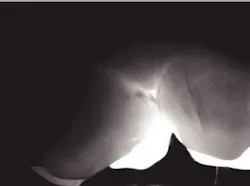

Accurate diagnosis of occlusal caries is problematic at best. Prior to fluoride, the explorer could be retained in an occlusal fissure by factors other than decay. Brown in The Journal of Dental Education (1993) had concerns relative to the reliability and validity of making a diagnosis of occlusal decay based on the retention of an explorer in an occlusal fissure.

By the time there is radiographic evidence of decay, much of the occlusal enamel is undermined. Occlusal decay in patients who have used fluoride in the early years of life has a different anatomical model. The fissures are not open, thus do not give easy access to the dental explorer. The carious lesion starts at the base of the fissure and spreads within the tooth. DIFOTI is particularly efficient in diagnosing this type of decay.

null

Many may say the above DIFOTI image (Fig. 2) only demonstrates stained fissures. The explorer would not enter the fissures at all. The DIFOTI diagnosis was confirmed with a Diagnodent reading in excess of 70. The tooth was restored in a minimally invasive fashion.